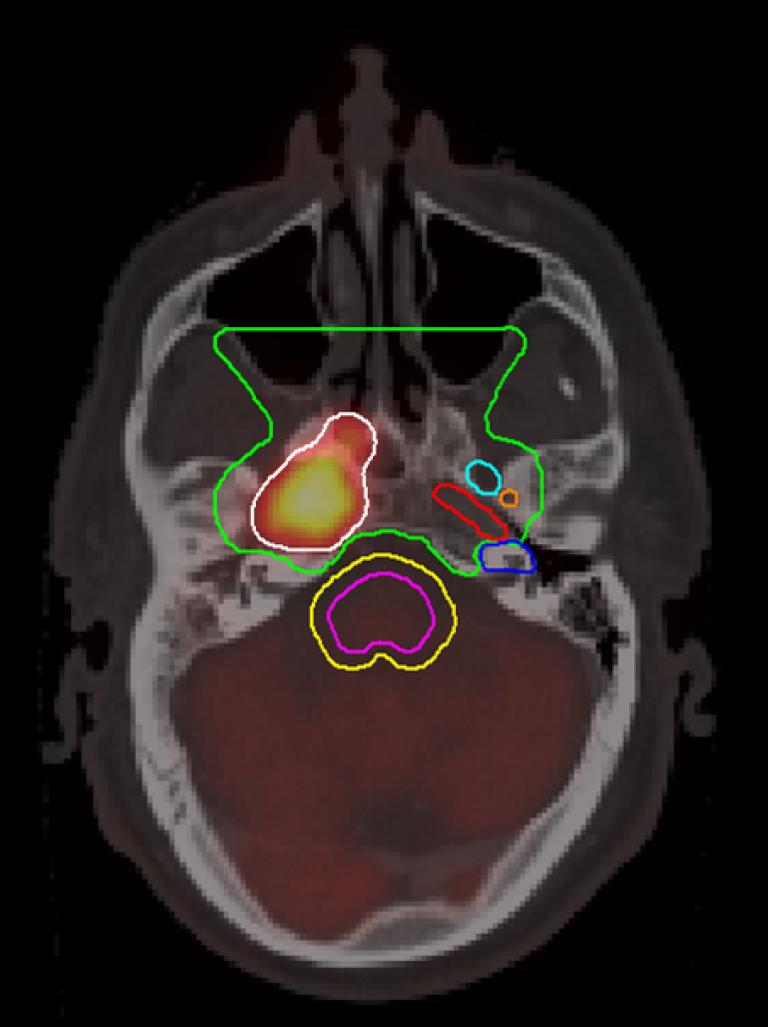

PET/CT

Metoden kombinerer Positronemisjonstomografi (PET) med Computertomografi (CT). En positronemitterende radionuklid koples til en markør, og det er vevsoppladningen av denne (vanligvis sukkeranalogen Fluordeoxyglykose (FDG)) som avbildes i PET-delen av maskinen. I samme seanse gjøres det også et CT-opptak for bedre anatomisk kartlegging. FDG-opptaket er avhengig av metabolsk aktivitet, og er ikke kreftspesifikt. CT-delen av maskinen er lik de som benyttes ved ordinære CT-undersøkelser, og det er mulig å integrere diagnostisk normaldose CT med jodkontrastmiddel som en del av PET/CT-undersøkelsen, vanligst gjøres det imidlertid lavdose-CT, som isolert sett ikke har særlig diagnostisk verdi.

Metoden har foreløpig ingen veldefinert plass internasjonalt i utredning av ØNH-kreft, men brukes blant annet ved utredning av ukjent primærtumor og ved responsevaluering.

Fordeler

- Metoden kombinerer anatomisk og funksjonell avbildning, og kan supplere ren morfologisk diagnostikk på CT og MR, særlig i tilfeller hvor postoperative og postradiære forandringer derangerer anatomiske strukturer.

- Metoden er aktuell ved T-staging spesielt i stadium III–IV preoperativt, ved ukjent primærtumor og ved doseplanlegging.

- PET/CT er en helkroppsundersøkelse, og kan benyttes for påvisning av fjernmetastaser og synkrone primærtumorer.

Generelle anbefalinger om bruk av FDG PET/CT

- Ved ukjent primærtumor, hvor standard utredning inkludert CT og MR ikke er konklusiv.

- For utredning av M-stadium ved lokalavansert tumor hvis behandlingen antas å bli endret ved påvisning av fjernmetastaser.

- For utredning av N- og M-stadium hvis standard utredning, inkludert CT og MR, ikke er konklusiv, og hvis behandlingen antas å bli endret ved påvisning av metastaser.

- Ved mistanke om resttumor, eller residiv, hvis annen modalitet ikke er konklusiv (forutsatt minst 12 uker etter avsluttet behandling) og hvis det planlegges kurativ behandling.

- PET/CT gjøres som responsevaluering 12–14 uker etter avsluttet kjemoradioterapi ved N-positiv sykdom, og vurderes ved ukjent primærtumor for å avklare N-status og i metastaseutredning.